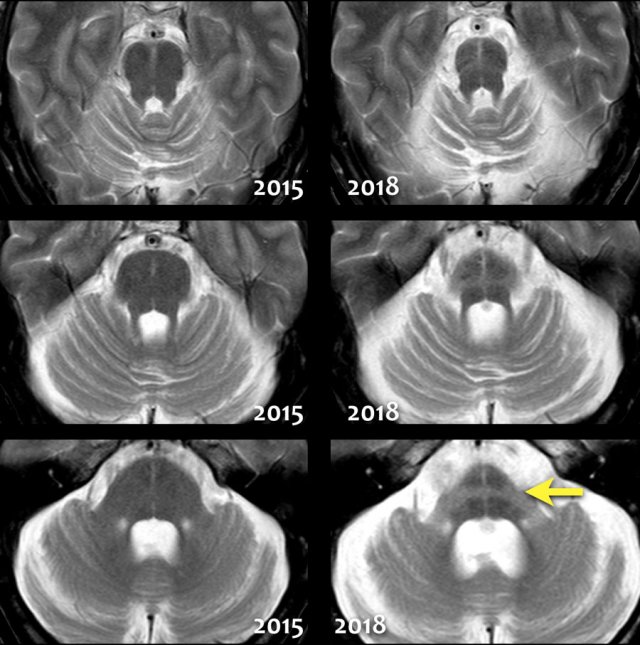

Multi System Atrophy (MSA)

MSA is also one of the atypical parkinsonian syndromes.

MSA is a rare neurological disorder characterized by a combination of parkinsonism, cerebellar and pyramidal signs, and autonomic dysfunction.

MSA can be classified as MSA-C, MSA-P or MSA-A.

In MSA-C (formerly known as sporadic olivopontocerebellar atrophy or sOPCA) the cerebellar symptoms predominate, whereas in MSA-P the parkinsonian symptoms dominate (MSA-P was formerly known as striatonigral degeneration).

MSA-A is the form in which autonomic dysfunction predominates and is the new term for what was formerly known as Shy-Drager syndrome.

In MSA there is pronounced cerebellar atrophy and severe atrophy of the pons.

In MSA-P: low T2 SI dorsolateral putamen and slit-like increased SI lateral to putamen on T2.

In contrast to PSP, we don't see the humming bird sign, because the midbrain has a normal convex upper border.

The so-called 'hot cross bun sign', which is a result of pontine hyperintensity, is typical for MSA-C.

Notice the extreme atrophy of the pons and the cerebellum in this patient when we compare images of 2015 with images of 2018.